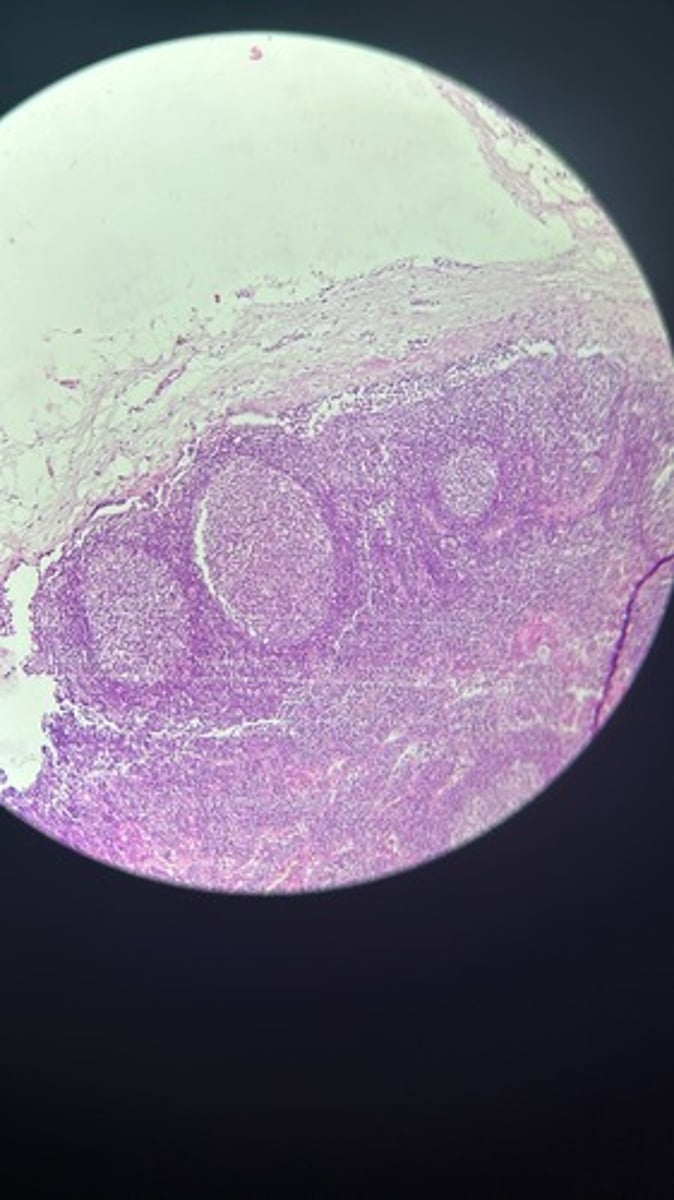

Lymph node HE

Lymph node HE

Lymph node HE

lymph node HE

Lymph node HE

Lymph nodes HE